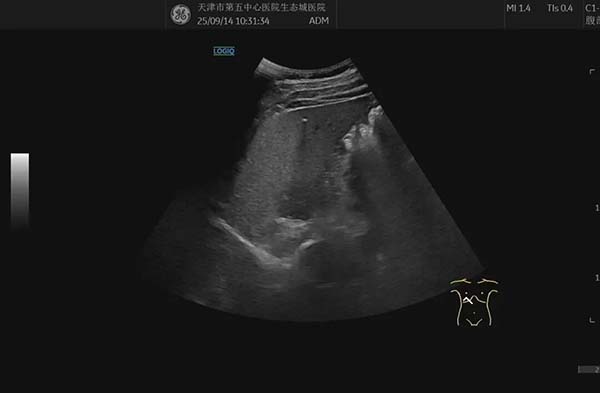

简单来说,肝内钙化灶就是肝脏某些部位出现了微小的钙盐沉积。在超声图像上,它们看起来像一个个亮白色的小点或小斑块。

它不是肿瘤,也不是活动性肝病,更像是肝脏过去某次轻微损伤后,在愈合过程中留下的一道“小疤痕”。就像皮肤受伤结痂脱落会留下印记一样,肝内钙化灶就是肝脏内部的“静态印记”,只是这个印记里含有钙质。